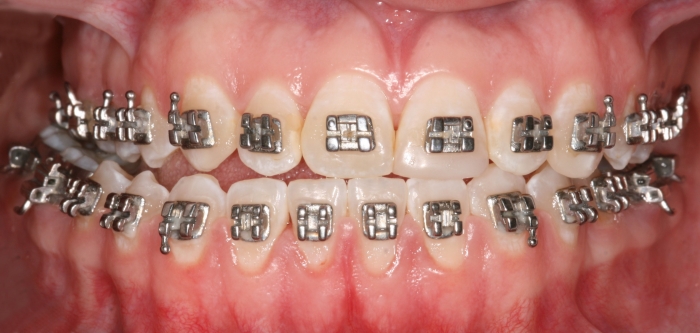

Mordida inicial - Clínica Cliniface

Mordida inicial